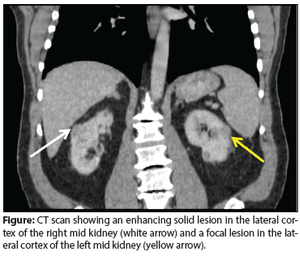

A 69-year-old man presented in the urology clinic for evaluation of bilateral renal masses, discovered incidentally during routine exams for follow-up of his chronic kidney disease.